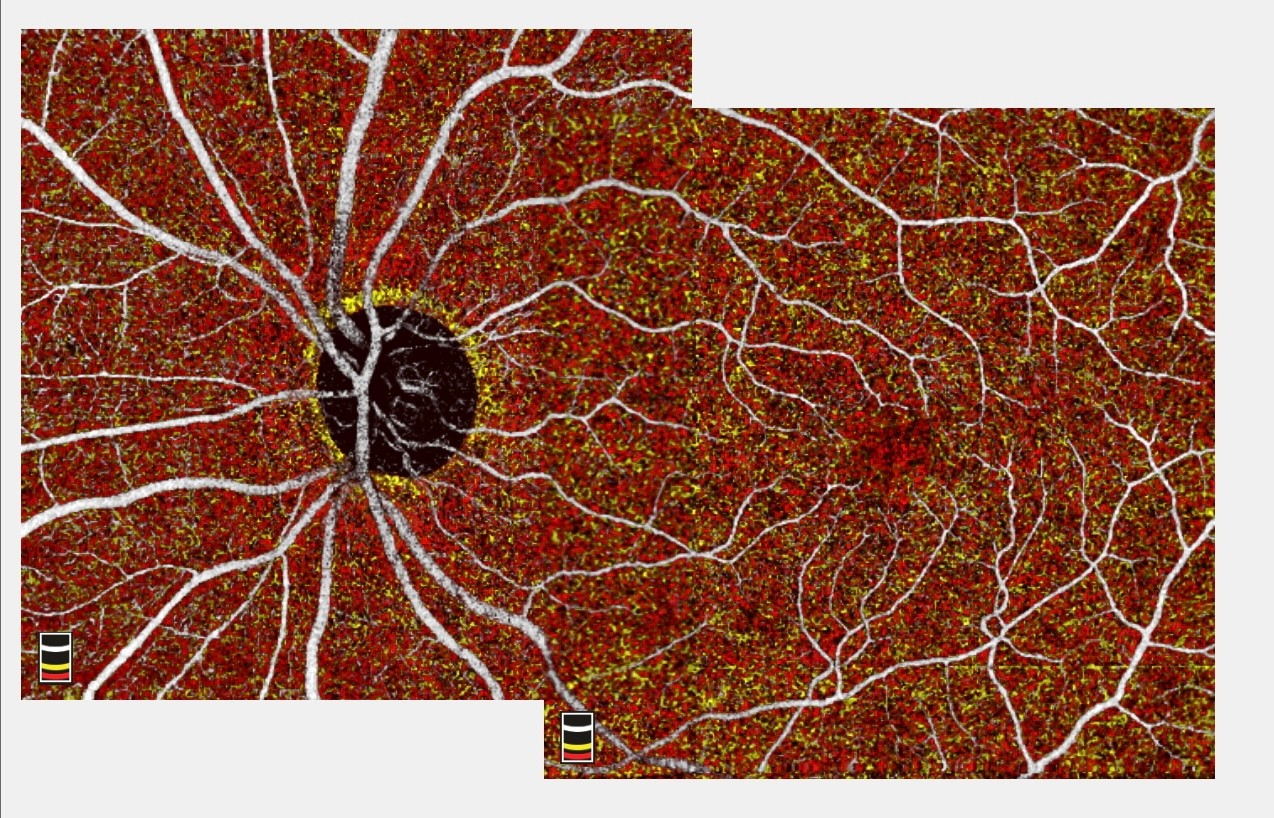

La OCT-A en el glaucoma nos permite hacer una evaluación y seguimiento de la microcirculación del nervio óptico.

La evaluación de la circulación en el polo posterior del globo ocular es crítica en la valoración clínica de los pacientes.

La OCT-A, es una nueva tecnología que permite hacer angiografía de coroides, retina y nervio óptico basada en tecnología de OCT. La OCT-A permite detectar el flujo vascular no solo en los grandes vasos de la coroides y de la retina, sino también en los capilares. Con esta tecnología no es necesaria la inyección de medios de contraste en la circulación del paciente para la adquisición de imágenes, lográndose imágenes de angiografía de alta resolución y en 3D.